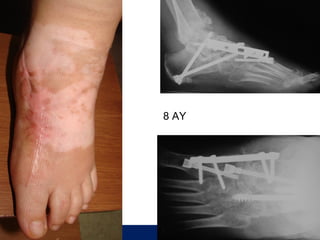

8.ay

8 AY

OLGU No 4

FK, 51y, K

10 yıldır oralad